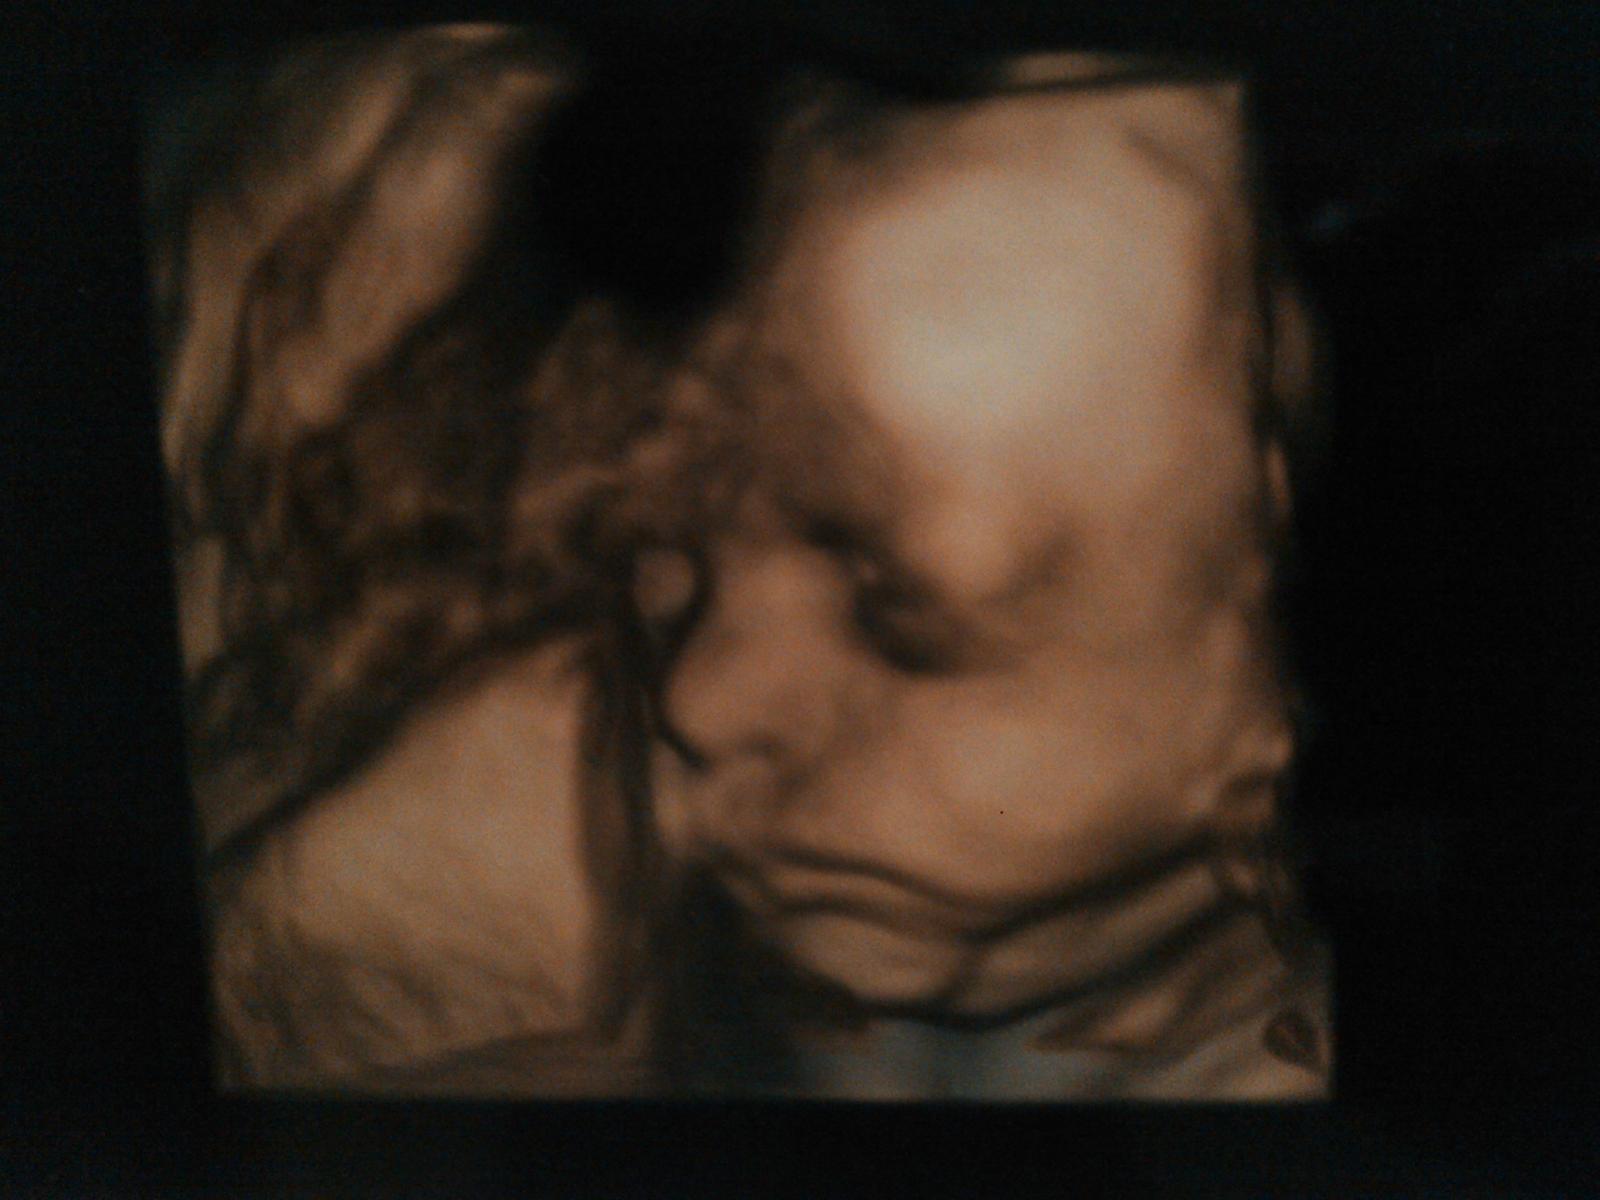

@archanjel007 moj prvy ( 22tt.) a druhy syncek (29tt.) na 3D sone ❤...a prve pohyby ako prvorodicka som mala v 18tt...No je to individualne, niektore zeny citia az okolo 23tt 😉...No nemusis sa sledovat, ked Ta prvykrat necakane kopne, tak Tebe sa v tom momente zastavi cas a budes v uzase z tejto carovnej chvile...Urcite to "nepresvihnes" 😉